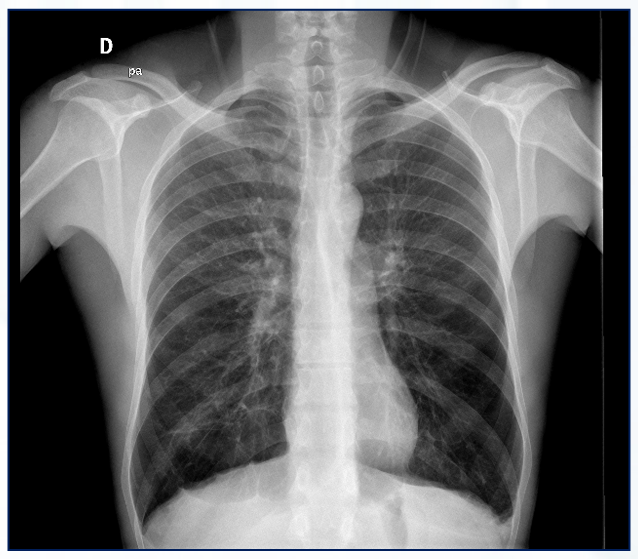

Quais os achados do Rx de tórax PA e perfil?

Hiperinsuflação pulmonar em paciente com quadro de exacerbação aguda de asma.

Hiperinsuflação transitória, apresentando

melhora após o tratamento do quadro agudo.